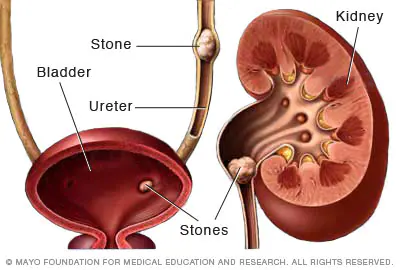

سنگ هاي کلیوي ذرات کوچک و سختی هستند که در یک یا در دو کلیه تشکیل شده و گاهی به داخل حالب ها ( لوله هاي عضلانی باریکی که ادرار را از کلیه ها به مثانه منتقل می کنند ) انتقال می یابند.

شناخت انواع سنگ ھای کلیه

سنگ کلیه شاخ گوزنی (stag horn)

علائم شایع سنگ کلیه که باید بدانید

ادرار مکرر و پرسوزش

خون در ادرار

کاھش دفع ادرار و یا قطع کامل آن

عوارض سنگ کلیه: چه مشکلاتی میتواند ایجاد کند؟

انسداد شدید مجاري ادرار

ھیدرونفروز

چگونه سنگ کلیه تشخیص داده میشود؟

سنگ ھای کلیه، به ندرت قبل از اینکه شروع به ایجاد درد کنند تشخیص داده می شوند.

این درد، معمولا آن قدر شدید است که بیمار را به بخش اورژانس فرستاده و در آنجا تست ھای زیادی می تواند وجود سنگ را معلوم کند.

این تست ھا ممکن است CT scan، اشعه ایکس، اولتراساوند(ultrasound) و آنالیز ادراری باشد.